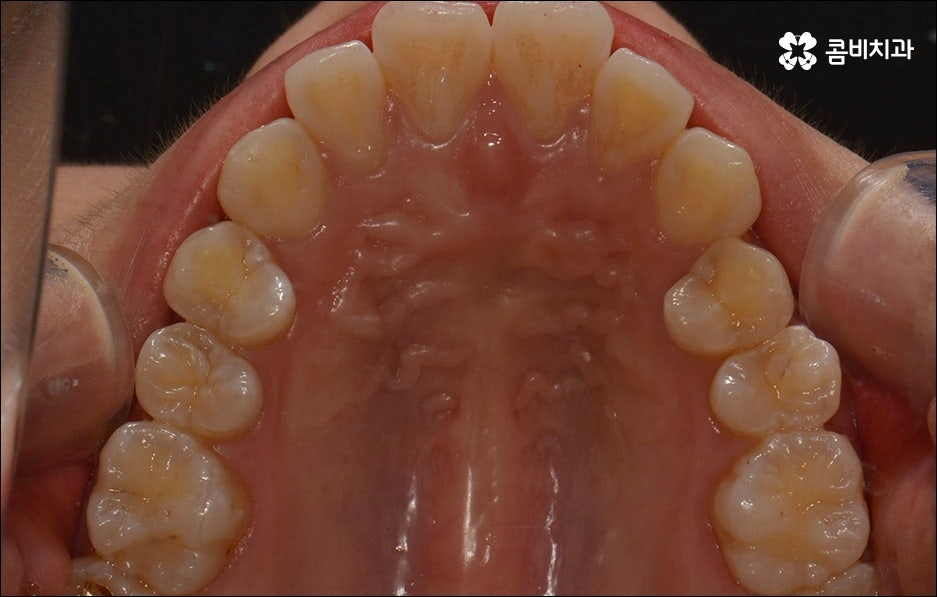

치열이 불규칙하여 기능적 심미적인 불편을 겪는 분들 중에 교정 치료를 고민하시는 분들이 많이 있습니다. 특히 앞니는 다른 치아보다 훨씬 외부에 잘 드러나므로 대화하거나 웃을 때 만약 앞니 사이가 벌어져 있거나 앞니 돌출 이 된 경우, 비틀어진 경우에는 신경이 많이 쓰일 수 있는데요. 하지만 막상 교정을 시작 하려고 하면 기간이 오래 걸리는 것 때문에 또는 치료 과정 자체에 부담을 느껴서 망설이시는 분들도 있을 수 있어요. 이때 앞니 외 다른 치아 배열 또는 위아래 교합에는 별다른 이상이 없다면 문제가 있는 앞니만 부분교정으로 치료할 수 있으니 이에 대해서 한 번 알아보시면 도움이 되실 거예요.

앞니가 튀어나오는 원인은 무엇일까요? 앞니 돌출 의 원인은 치아 크기가 큰 데 반해서 골격이 많이 작거나 상하악골 크기 차이가 많이 나는 것처럼 유전적인 요소에 기인하는 경우가 많으나 후천적인 생활 습관으로 인해서 발생하고 강화될 수도 있기 때문에 주의하실 필요가 있어요. 예를 들어 어릴 때 부터 손톱을 물어뜯거나 손가락을 자주 빠는 습관, 혀로 앞니를 밀면서 빼물곤 하는 습관을 가지고 있었다면 이로 인해 앞니가 튀어나올 수도 있는 거예요. 또한 축농증, 비염 등의 질환으로 인해 구호흡을 하게 되었다면 이것이 원인으로 작용할 수도 있으니 필요하다면 이비인후과와 협진을 하는 등 원인파악과 개선을 전반적으로 함께하시길 권유드리고 있어요.

하지만 보통은 돌출된 앞니 뿐 만 아니라 골격적인 부분이 원인이 되는 경우가 많으며 이런 경우에는 상태에 맞게 전체적으로 교정을 진행하여야 교합이 올바르게 되고 입매가 전체적으로 균형감 있게 개선될 수 있어요. 이런 경우에 골격적인 원인을 무시한 채 무리하게 치아의 각도만 안쪽으로 넣으려고 하면 자칫 옥니가 될 수도 있기 때문에 이러한 부작용을 막기 위해서도 환자분들의 상황을 정확하게 검진하고 그에 맞는 교정 플랜을 세우는 것이 필요한 거예요. 물론 부정교합 정도가 심각하고 골격적인 원인이 이미 굳어진 경우와 같이 수술이 함께 필요한 케이스도 있을 수 있으나 교정 치료만으로도 튀어나온 앞니가 들어가면서 자연스럽고 부드러운 인상으로 바뀌는 경우도 많으니 먼저 검진과 상담부터 꼼꼼하게 진행해 보시길 권유드리고 있습니다. 특히 개개인의 치열, 교합, 잇몸 상태, 구강구조 등을 면밀하게 파악하고 그에 따른 정확한 치료 계획을 수립할 수 있는 경험 많은 의료진과 함께 하는 것이 중요할 수 있어요.

골격적인 부분이 원인이 되는 경우 치료 시기 역시 중요할 수 있는데요. 성장기가 끝나고 잇몸뼈가 굳어지기 전에 상악과 하악의 균형잡힌 발달을 유도하는 것이 필요하기 때문에 윗턱에 비해 아래턱이 많이 작다면 2차 성징이 나타나기 전에 치료를 시작하는 것이 좋을 거예요. 2차 성장 시기는 성별 (여자 아이가 남자 아이보다 빠름) 및 개인마다 차이가 나지만 보통 10~12세 사이이니 필요하다면 이때 아이와 함께 치과에 내원하시길 추천드리고 있는데요. 돌출입 구조에 있어서 유전의 영향은 30% 정도이니 만약에 부모님께서 상악골이 돌출된 부정교합을 가지고 있다면 더욱 관심을 가지고 아이의 치열을 관찰하셔서 치료 시기를 조율해 보시는 게 좋을 거예요. 또한 상황에 따라 교정 치료 전에 충치나 잇몸을 먼저 치료하는 과정이 필요할 수 있으니 시작 시기나 전체 기간, 방법 등 자세한 사항들에 대해서 면밀한 검진 후 충분하게 상담부터 받아 보시길 권유드리고 있습니다.